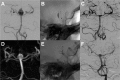

Figure 3

Unruptured aneurysm of the basilar artery at the ostium of the left superior cerebellar artery (A). In a first session, the aneurysm was treated with the remodeling, resulting in complete occlusion (B). A growing aneurysm recurrence (C) was treated 13 months after the initial intervention by placing a WEB SL device (D). A late phase control run depicted a slowed down intra-aneurysmal blood circulation (E). Six-month DSA follow-up shows a neck remnant (F).